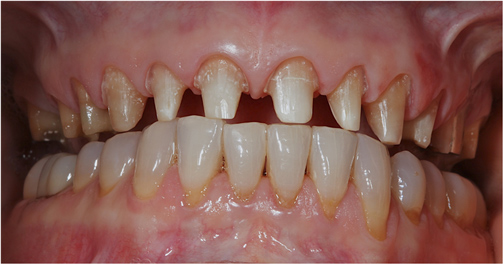

This patient previously presented with esthetic concerns but was reluctant to proceed with reconstructive dental treatment (Figure 19 and Figure 20). She had been monitored for several years and advised of the benefits of an interdisciplinary treatment plan including periodontal, dental implant, and prosthodontic therapy. The diagnosis included occlusal trauma, loss of vertical dimension, lack of posterior tooth support, and supra-eruption. There was also gingival asymmetry, lack of attached gingiva, lateral ridge defect for the mandibular left molar region, pneumatization of the maxillary right sinus, and alloy tattoo of the gingiva for the maxillary right bicuspids. Eventually the mandibular left second bicuspid, which was an abutment for a fixed partial denture, fractured, resulting in an abscess and significant bone loss localized to this abutment tooth (Figure 21). At this point, given the need for extraction and now more limited posterior chewing capability, the patient requested a comprehensive consultation and treatment plan for the reconstructive therapy she had previously elected to postpone.

Figure 20 Intraoral examination revealed multiple concerns, including loss of vertical dimension, lack of posterior tooth support, and supra-eruption. There was also gingival asymmetry, and minimal zones of attached gingiva.

Figure 20